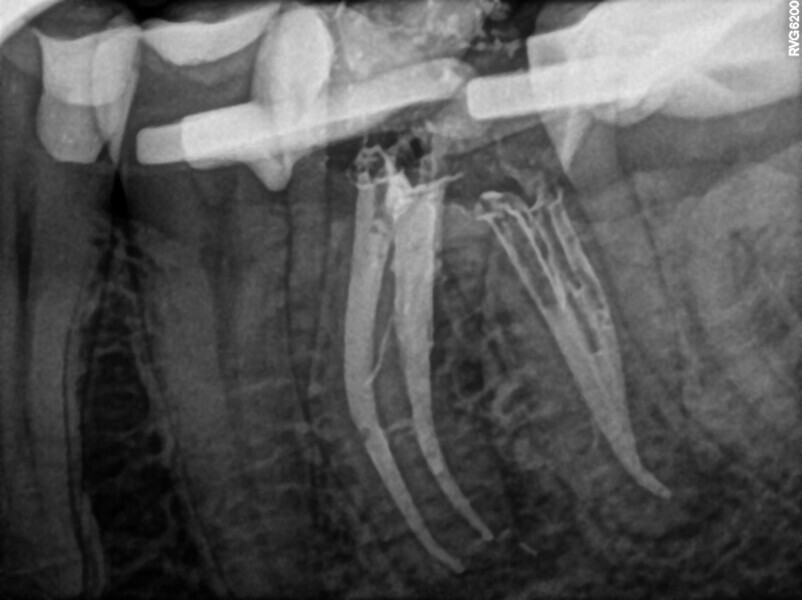

Fig. 13: Pre-op radiograph. Two pieces of the broken file visible.

After administering anaesthesia and placing a dental dam, the composite restoration was removed, and a temporary restoration with flowable composite and flowable dental dam for the root canal treatment was performed (Figs. 14–17). After removing the filling material from the mesiolingual and distal canals, access to the broken file was performed. The first piece of the instrument was removed with the ultrasonic tip (Fig. 18), and the tip of the second piece of the file then became visible. Unfortunately, the removed file piece broke in the middle and only the coronal part could be retrieved (Fig. 19). Because the apical part of the broken file was invisible and did not emerge from the canal during the irrigation and activation, an attempt at bypassing it was made. Analysis of the CBCT scan did not reveal a clear answer as to whether there was one apical foramen, so during the bypass procedure through the mesiolingual canal, a periapical radiograph was performed. The radiograph indicated that either there was a ledge in the apical area or there were two separate apical foramina (Fig. 20). For the irrigation protocol, the AutoSWEEPS mode was used at 1.2 W power with the flat SWEEPS 300/20 fibre tip. The tips of both mesial canals were placed below the orifice. The Less-Prep Endo protocol was performed twice in the manner described elsewhere.5 After the irrigation, irrigant flow between both canals was rapid.

The canals were dried with paper points and micro-suction (Fig. 21). After the irrigation protocol, there was still a lack of patency and tugback was achieved only in the mesiolingual canal. The mesiobuccal and distal canals were filled with an epoxy resin sealer and warm gutta-percha (squirting technique), and the mesiolingual canal was filled with a 30/.04 gutta-percha cone with the continuous wave of condensation technique (Fig. 22). A distally shifted periapical radiograph was performed (Fig. 23). The radiograph revealed a puff of sealer in the periapical area of the mesial root and the isthmus filled with the sealing material. A composite material was placed into the access cavity, and the patient was scheduled for the control appointment. At six months and 12 months, CBCT scans were performed (Figs. 24 & 25). The images found no signs of inflammation in the periapical area, and the tooth was asymptomatic.